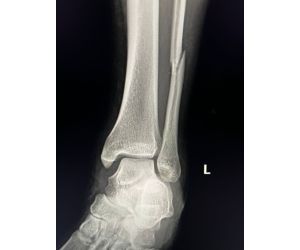

Persistent Lateral Ankle Pain in a Professional Athlete

Mohamed Elalfy

Case Discussion Persistent Lateral Ankle Pain in a Professional Athlete I would appreciate the opinion of MSK radiologists and foot & ankle...

Read more